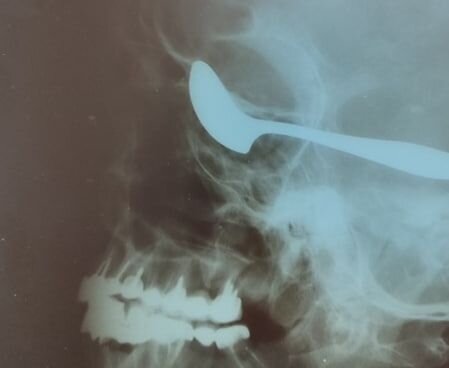

В Чувашии хирурги спасли зрение мужчине, вогнавшему себе в глаз ложку

Житель Чувашии вогнал ложку себе в голову во время приступа белой горячки. Врачи не только спасли ему жизнь, но и сохранили зрение, сообщает пресс-служба минздрава региона.

Мужчину госпитализировали в Алатырскую ЦРБ с панкреатитом, обострившимся на фоне злоупотребления алкоголем. Пациент провёл в хирургическом отделении несколько дней, а затем у него случился алкогольный делирий.

«Пациент сначала внезапно набросился на соседа по палате, а потом схватил ложку и вогнал её себе в глаз. После этого он упал и потерял сознание»,

— говорится в сообщении.

Так как мужчина находился в больнице, помощь ему оказали быстро. Врачи провели рентген и компьютерную томографию, а также вызвали нейрохирурга из республиканской клинической больницы.

После произошедшего пациент частично парализован. Ему предстоит реабилитация, добавили в минздраве.